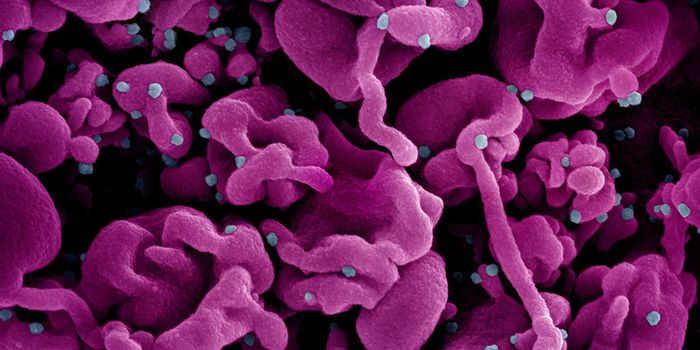

MAR 06, 2024Clinical & Molecular DXMany of us wanted to get a COVID-19 vaccine as soon as it was available, but someone took that to a wild extreme.